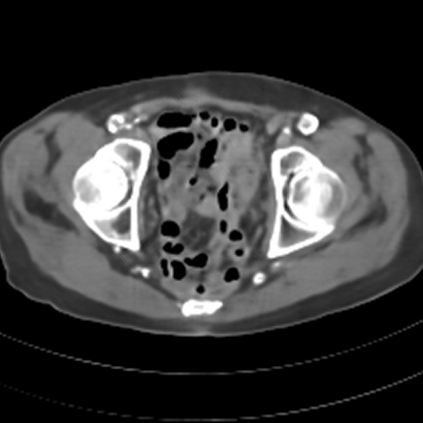

Sparse-view computed tomography (CT) -- using a small number of projections for tomographic reconstruction -- enables much lower radiation dose to patients and accelerated data acquisition. The reconstructed images, however, suffer from strong artifacts, greatly limiting their diagnostic value. Current trends for sparse-view CT turn to the raw data for better information recovery. The resultant dual-domain methods, nonetheless, suffer from secondary artifacts, especially in ultra-sparse view scenarios, and their generalization to other scanners/protocols is greatly limited. A crucial question arises: have the image post-processing methods reached the limit? Our answer is not yet. In this paper, we stick to image post-processing methods due to great flexibility and propose global representation (GloRe) distillation framework for sparse-view CT, termed GloReDi. First, we propose to learn GloRe with Fourier convolution, so each element in GloRe has an image-wide receptive field. Second, unlike methods that only use the full-view images for supervision, we propose to distill GloRe from intermediate-view reconstructed images that are readily available but not explored in previous literature. The success of GloRe distillation is attributed to two key components: representation directional distillation to align the GloRe directions, and band-pass-specific contrastive distillation to gain clinically important details. Extensive experiments demonstrate the superiority of the proposed GloReDi over the state-of-the-art methods, including dual-domain ones. The source code is available at https://github.com/longzilicart/GloReDi.